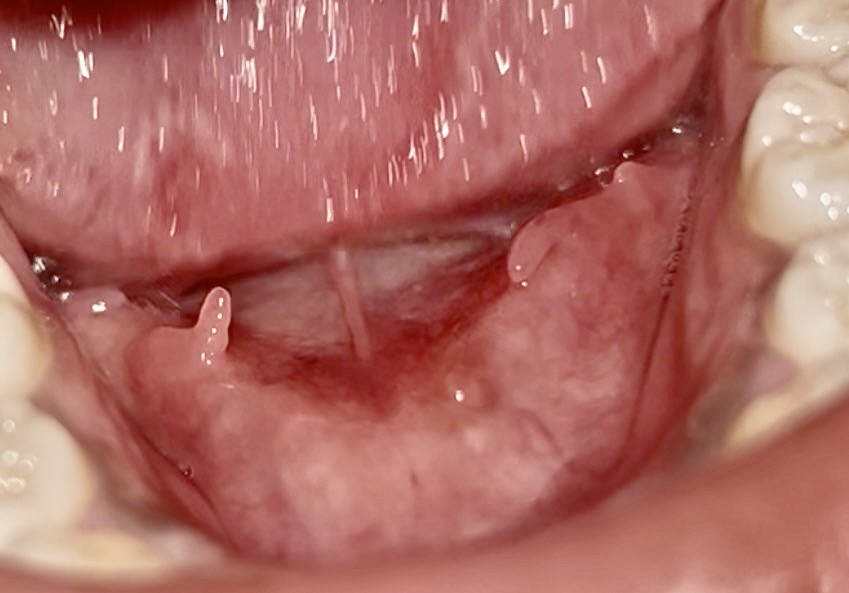

20 มีนาคม 2569 11:46:27 #1 มันคืออะไรคะ ไม่มีอาการเจ็บ https://haamor.com/media/create_topic/20260320113343.jpeg

| อายุ: 22 ปี เพศ: F น้ำหนัก: 22 กก. ส่วนสูง: 168ซม. ดัชนีมวลกาย : 7.79 (ค่ามาตรฐานคนเอเชีย=18.5-22.9) | |